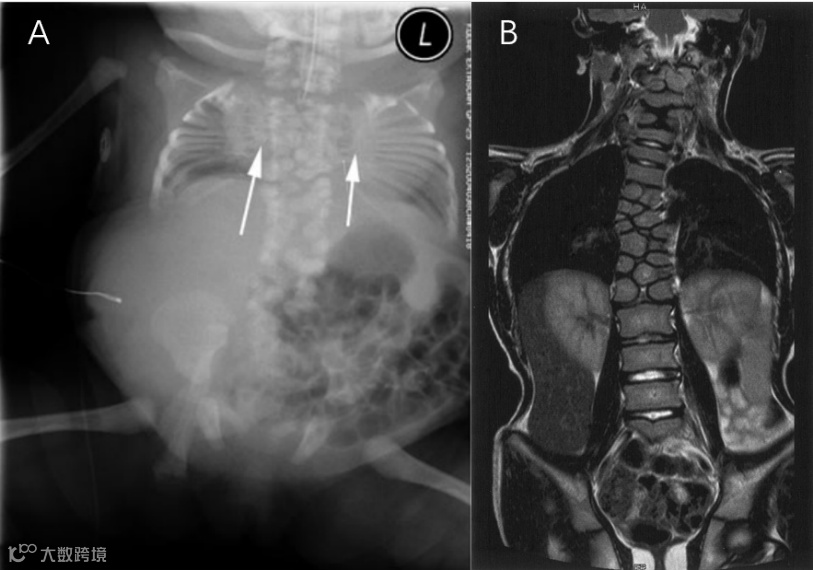

SCDO4型患者的所有椎体畸形程度都异常严重。与SCDO1相比,椎弓根相对突出(“蹦床”特征)。

SCDO4型

SCDO5型患者临床症状出现更早,以下半段脊柱的半椎体和蝴蝶椎为典型特征。

SCDO6型:复杂的颅颈交接区畸形,C1-C3的后半部分缺失,C4和T9为左半椎,T4为右半椎